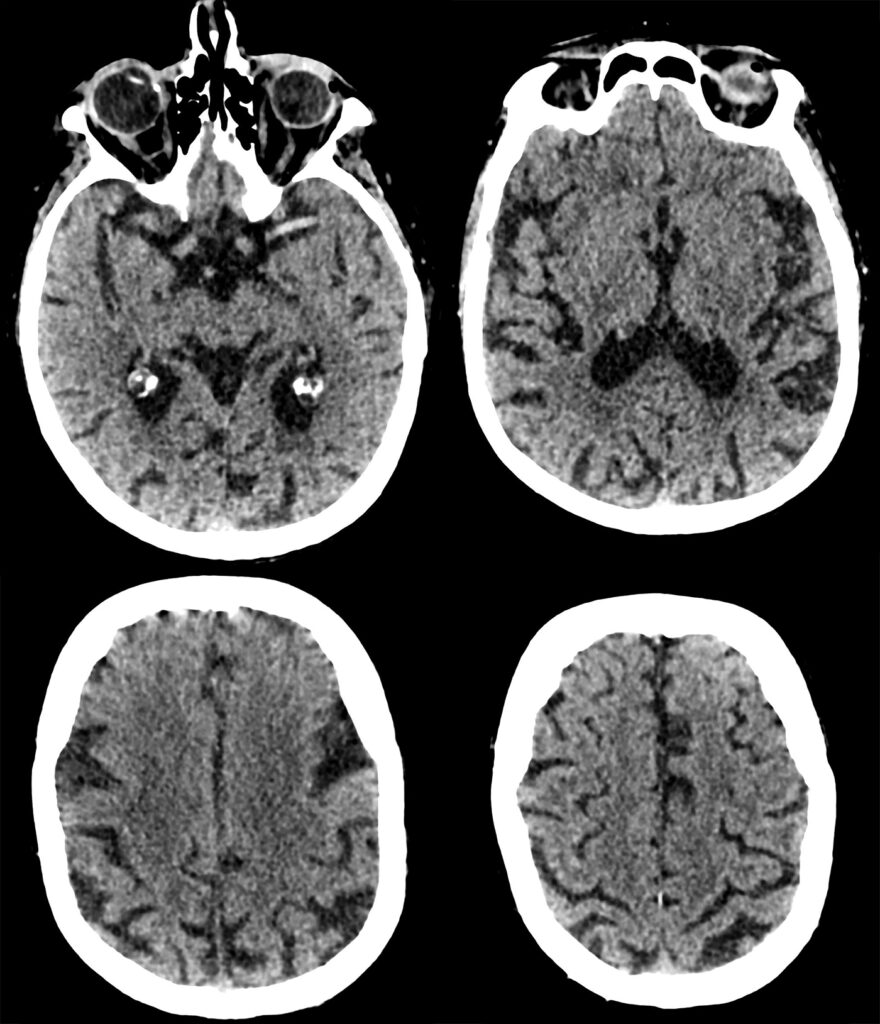

What abnormalities if any can you see?

What abnormalities if any can you see?

Now 1 hr 20 mins (80 mins) since onset, BP currently 160/90, NIHSS unchanged at 3.